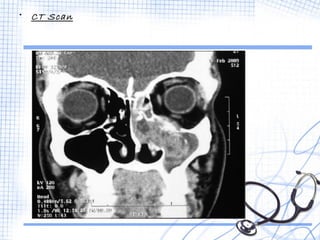

• CT Scan